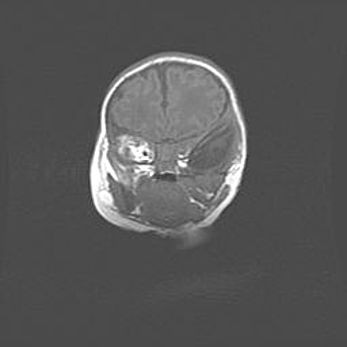

Множественные кисты обоих полушарий головного мозга, наибольшая из них в правой затылочной области. Ассиметричная атрофическая гидроцефалия.

Возраст: 7 месяцев

Вес: 5660 г

Пол: мужской

Окружность головы: 41,5 см

Срок гестации: 28-29 недель

Кисты головного мозга развиваются в результате многоочаговых некрозов вещества мозга и возникают вследствие перенесенной перинатальной инфекции, менингитов, энцефалитов, асфиксии, родовой травмы, расстройств мозгового кровообращения различного генеза. Образованию кист в веществе головного мозга плодов и новорожденных способствуют такие факторы, как высокое содержание в нем воды, недостаточная (или отсутствие) миелинизация и слабая астроглиальная реакция на повреждение.

Кисты могут сочетаться с гидроцефалией и другими поражениями головного мозга.